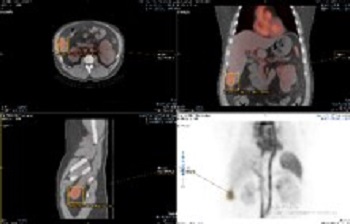

Mirada

Enhanced user experience for NM reading with a leading NM viewing solution

A comprehensive NM solution, designed to enhance productivity of PET/CT and NM reading. It offers a solution for handling multiple studies requiring rigorous quantification of MV data.